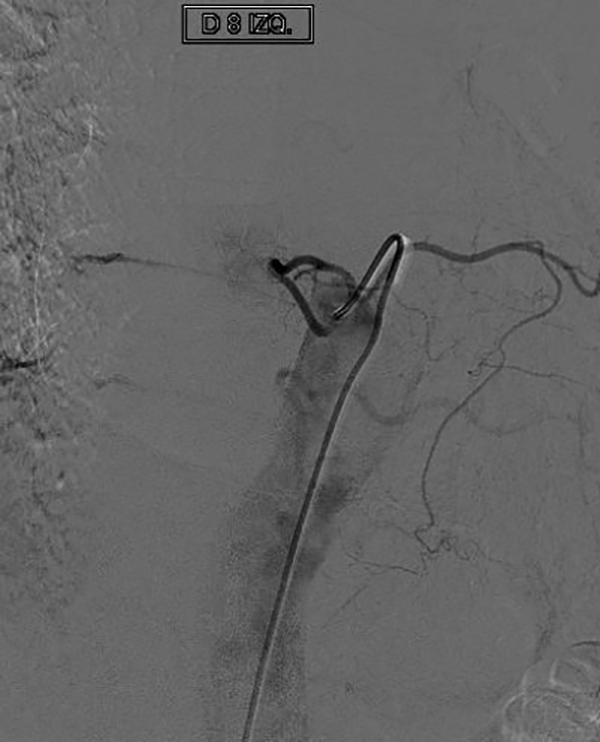

Figura 8: Caso #1. ADM postoperatoria alejada que demuestra la ausencia de la FDAVE en D8 izq.

CASO #1. Paciente masculino de 52 años con una historia de 6 meses de evolución de disestesias en ambos miembros inferiores, inestabilidad en la marcha, hiperreflexia y urgencia miccional. Se estudió con RMN (Fig. 3), ARM (Fig. 4) y ADM seguida de embolización con oclusión total de una FDAVE D8 izq. (Fig. 5). Evolucionó sin déficit y a los 11 meses comenzó con la misma sintomatología previa a la embolización. Se estudió nuevamente y la ADM (Fig. 6) mostraba la recidiva de la FDAVE y fue derivada para microcirugía (Fig. 7). Luego de la cirugía evolucionó sin déficit, se realizó una ADM diferida (Fig. 8) y lleva 116 meses libres de enfermedad.